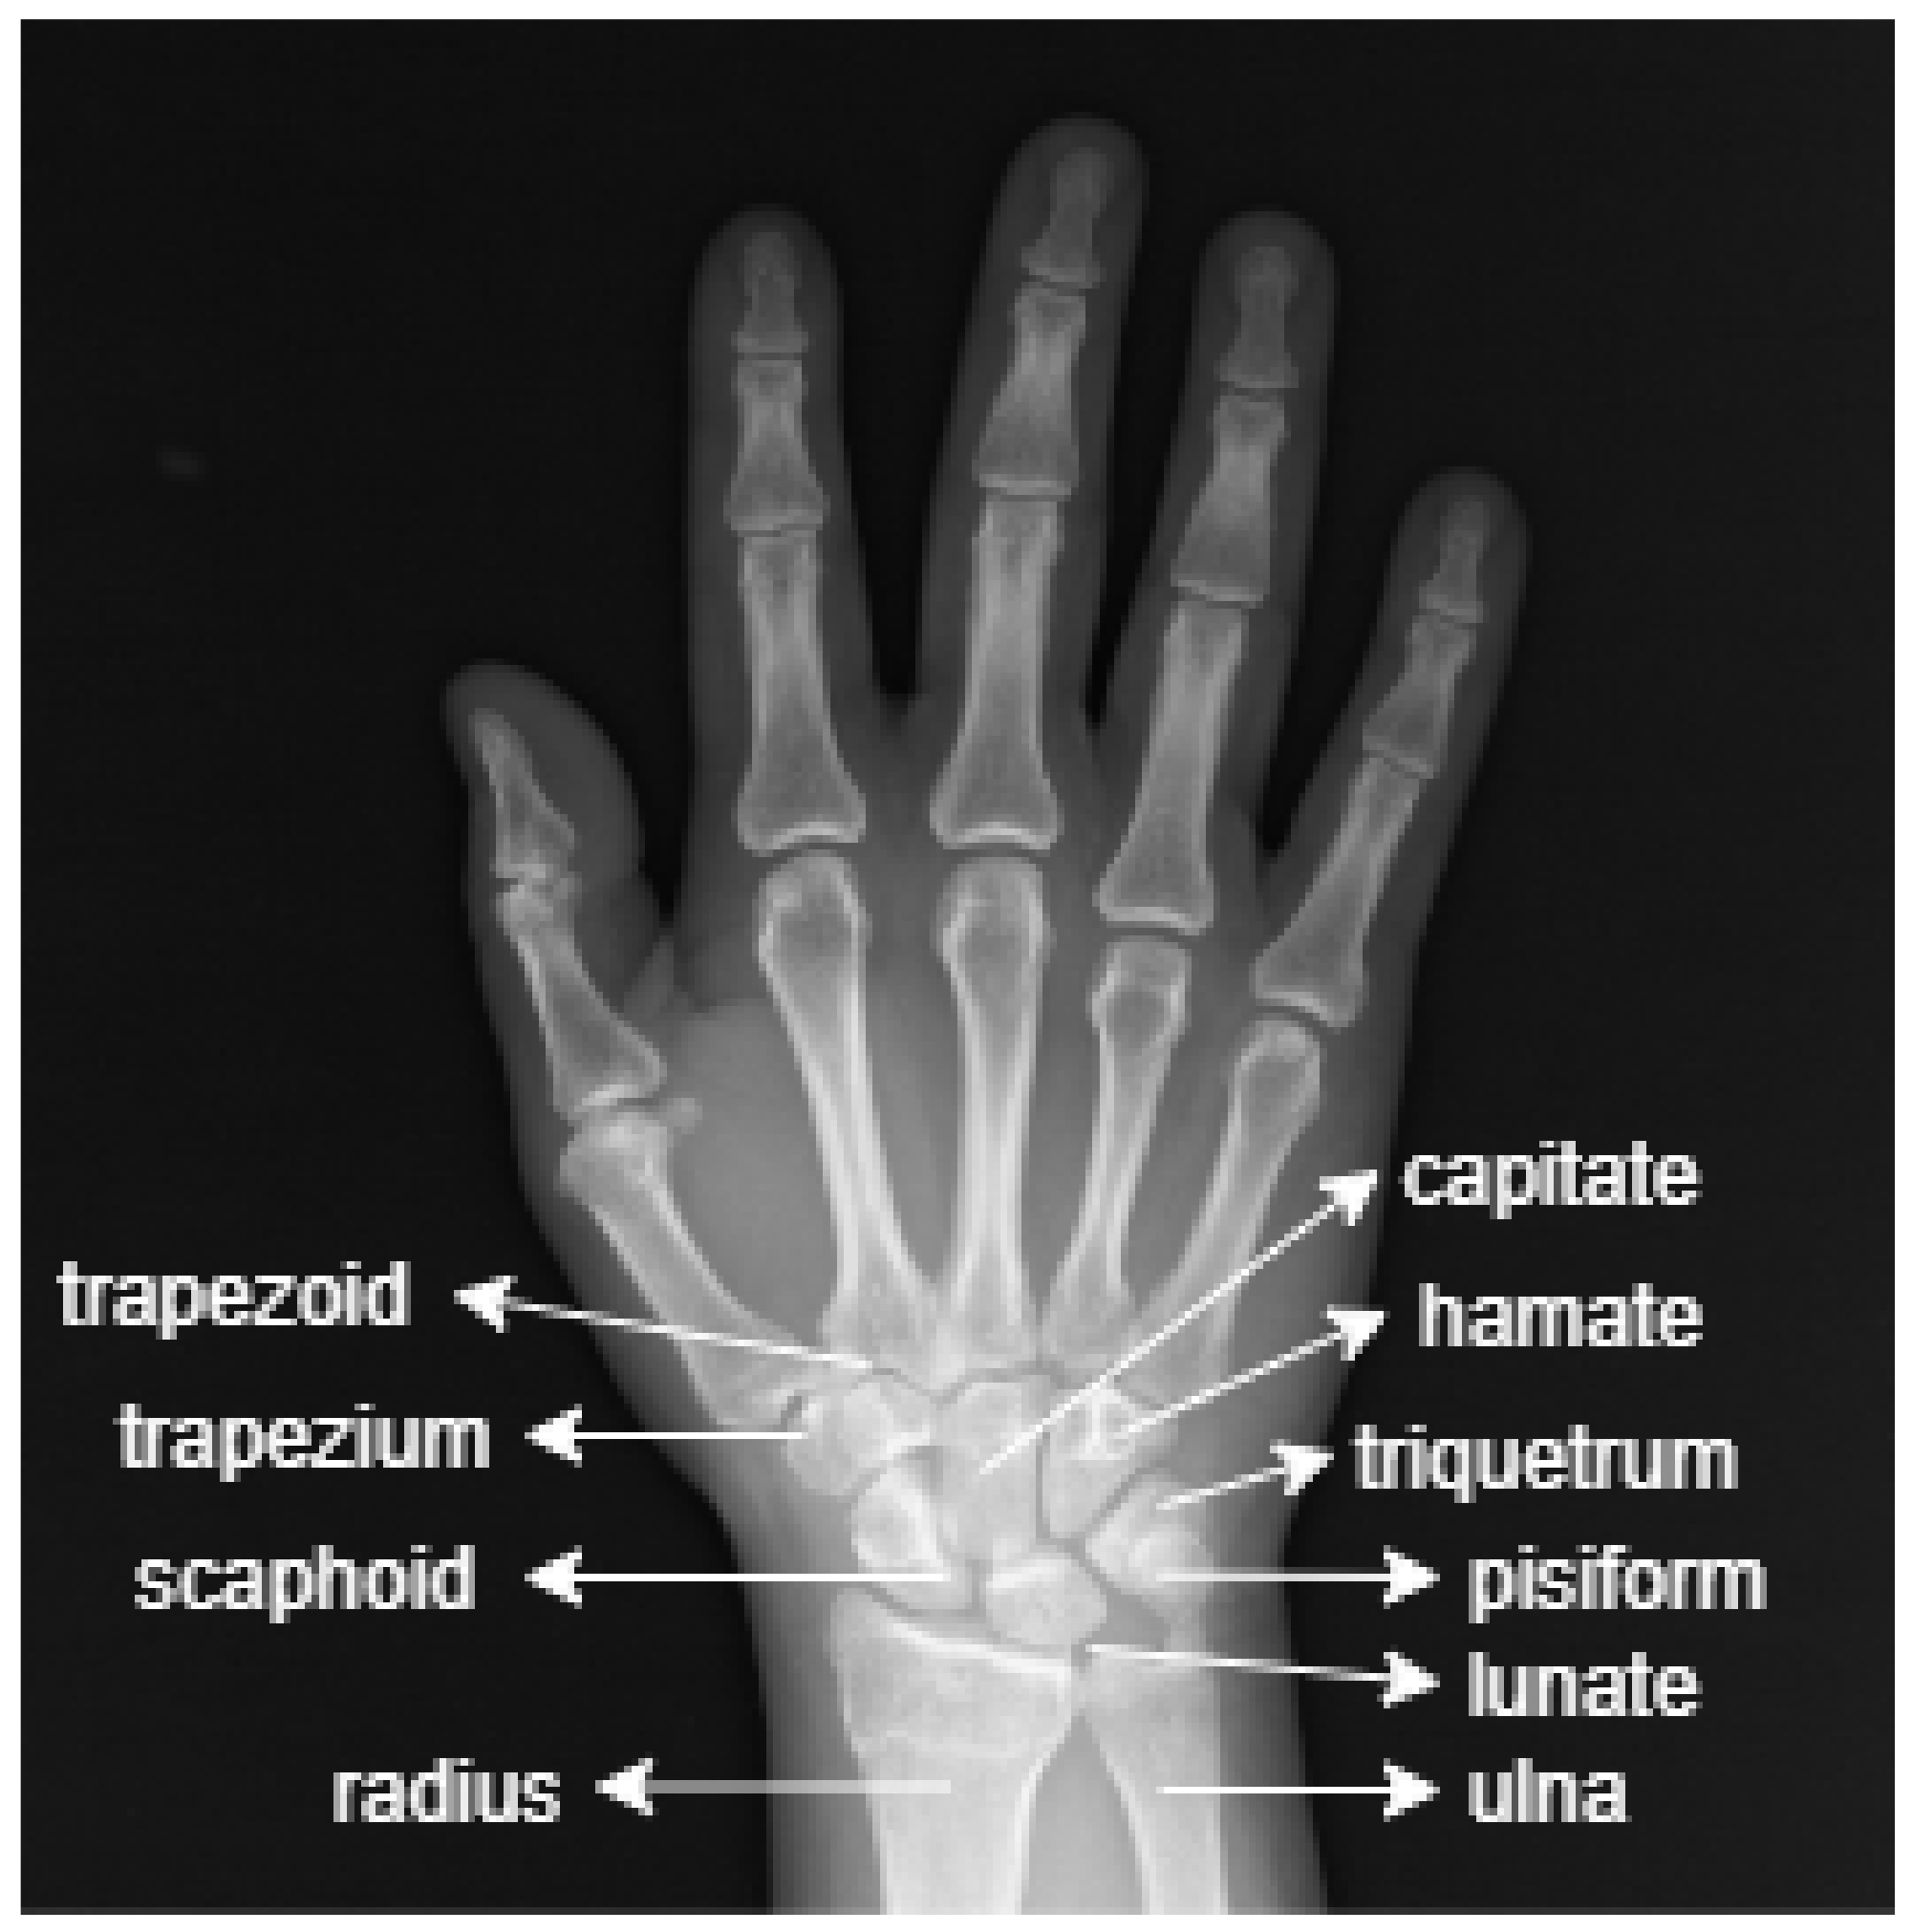

Sinishlar — bu suyak to‘qimasining uzilishi bo‘lib, u ko‘pincha travma, yiqilish yoki to‘qnashuv natijasida yuzaga keladi. Rentgen tekshiruvi bu sinishlarni ko‘rish va davolash strategiyasini belgilashda muhim ahamiyatga ega.

Raqamli rentgen tekshiruvi an'anaviy rentgenga qaraganda kamroq nurlanish bilan yuqori aniqlikda tasvir beradi. Bu orqali suyakning qanday sinib, qanday joylashganini aniq ko‘rish mumkin.